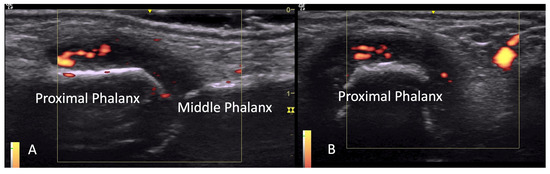

2.2. Tendon Pathology

2.2.1. Tenosynovitis

2.2.2. Contractures and Tendon Friction Rubs